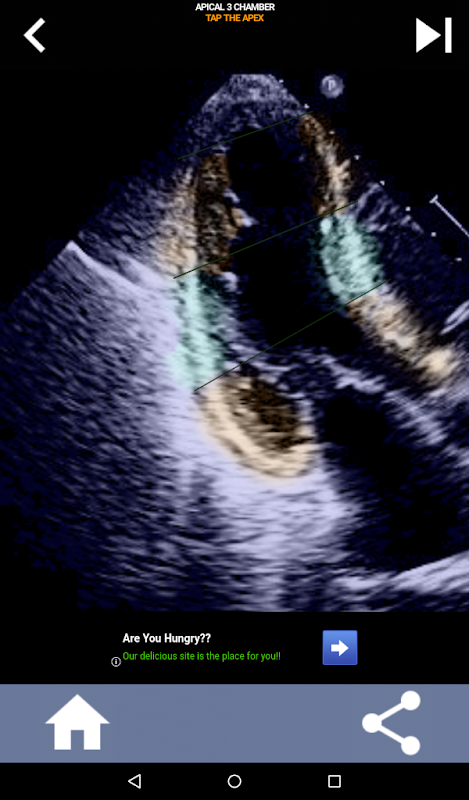

Quiz-gebaseerde visuele benadering voor het leren van de AHA-hartsegmenten: echocardiografie

Deze app test je kennis met behulp van echte echobeelden, wat ik vaak de beste lesmethode vind.